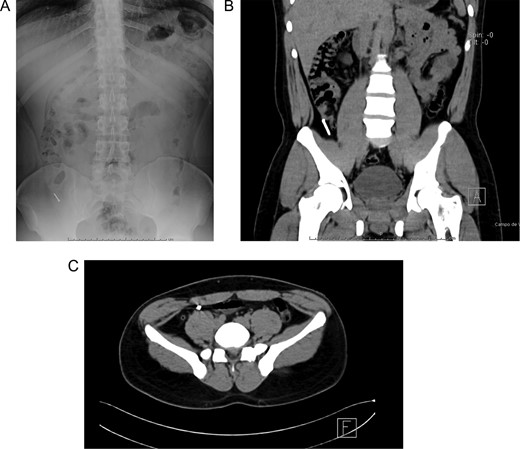

Patient is a 27-year-old male without past medical history. During his annual routine medical examination, an abdominal X-ray was requested. A metallic foreign body (30 mm nail) was discovered in his lower right abdomen (Fig. 1A). With these findings, he was transferred to our hospital. On arrival, he was completely asymptomatic, and he had no recollection of having swallowed the nail. Abdominal examination was unremarkable, and he had no evidence of any surgical scars. With these findings, a contrast-enhanced abdominal computed tomography (CT) revealed the presence of a 30 mm metal nail inside his appendix (Fig. 2A). The appendix had an outer diameter of 5 mm and was surrounded by homogeneous, non-inflamed fat and contained intraluminal air (Fig. 3A). A colonoscopy was requested to assess the cecum to try to remove the foreign body, however, after reaching the cecum and the appendix the nail could not be found (Fig. 1B). An intraoperative abdominal x-ray was needed, which confirmed the presence of the nail in the appendix (Fig. 2B).

(A) Abdominal X-ray with a radiopaque metallic foreign body. (B) Abdominal CT, the metallic foreign body is lodged in the appendix. (C) Abdominal CT, the appendix is surrounded by homogeneous non-inflamed fat and contains intraluminal air.